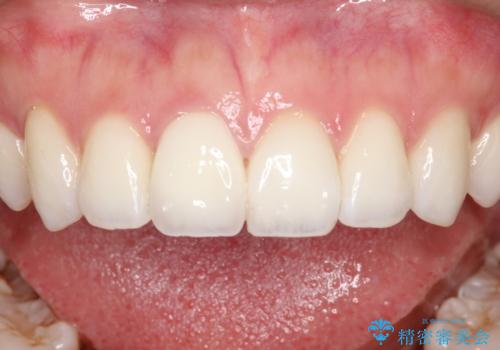

【オールセラミッククラウン】前歯の被せ物

オールセラミック(スペシャル)にて修復しております。

オールセラミッククラウンは切縁の透明感や色調のグラデーションを再現することができます。